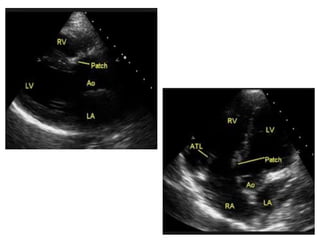

• TR is commonly encountered in patients with repaired TOF

and may be due to several factors.

• One mechanism involves disruption of the integrity of the

tricuspid septal-anterior commissure by the VSD patch. This

results in a TR jet originating at the junction between the VSD

patch and the septal attachment of the TV and extending

along the atrial septum.